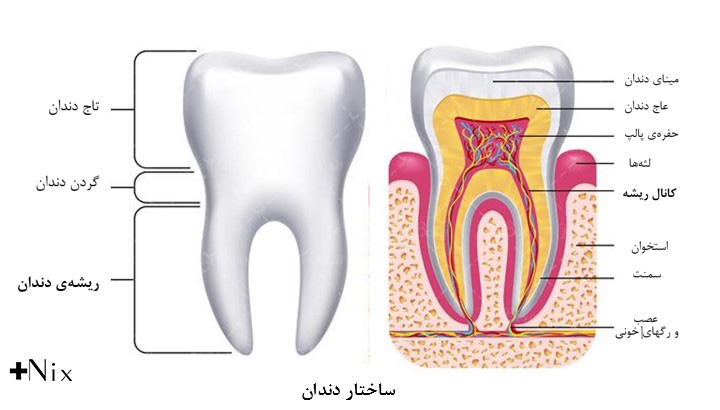

بسیاری از بیماران در مورد تفاوت کانال و ریشه دندان سردرگم هستند. در واقع، این دو مفهوم کاملاً متفاوتاند اما در زبان روزمره بهجای هم استفاده میشوند. به زبان ساده: ریشه دندان بخشی از ساختار فیزیکی دندان است که در استخوان فک قرار دارد و دندان را محکم نگه میدارد، در حالی که کانال ریشه یک فضای توخالی در داخل ریشه است که شامل پالپ، عصبها و رگهای خونی میشود. دانستن تفاوت کانال و ریشه دندان برای درک بهتر درمانهای دندانپزشکی مانند درمان ریشه یا روت کانال تراپی اهمیت زیادی دارد.

ریشه دندان (Tooth root)

ریشه، بخشی از دندان است که زیر لثه قرار دارد و آن را به استخوان فک متصل میکند. هر دندان میتواند یک یا چند ریشه داشته باشد. سطح ریشه با مادهای به نام سیمان دندانی پوشیده شده و از طریق رباطهای پریودنتال به استخوان فک متصل میشود.

کانال ریشه (Root canal)

کانال ریشه دندان همان مجرای درون ریشه است که پالپ (عصب، بافت همبند و رگهای خونی) در آن قرار دارد. ساختار کانال ممکن است ساده یا بسیار پیچیده باشد. پیچیدگی آن نقش مهمی در موفقیت درمانهای اندودنتیک دارد.